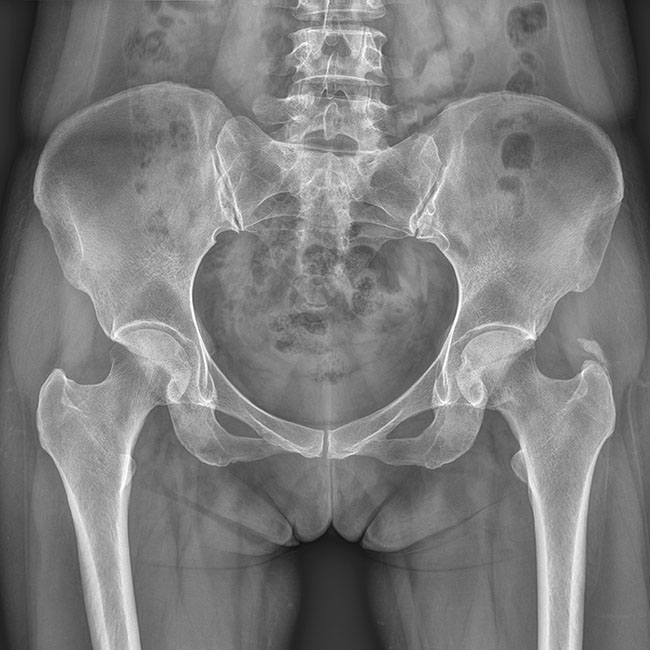

臨床圖片